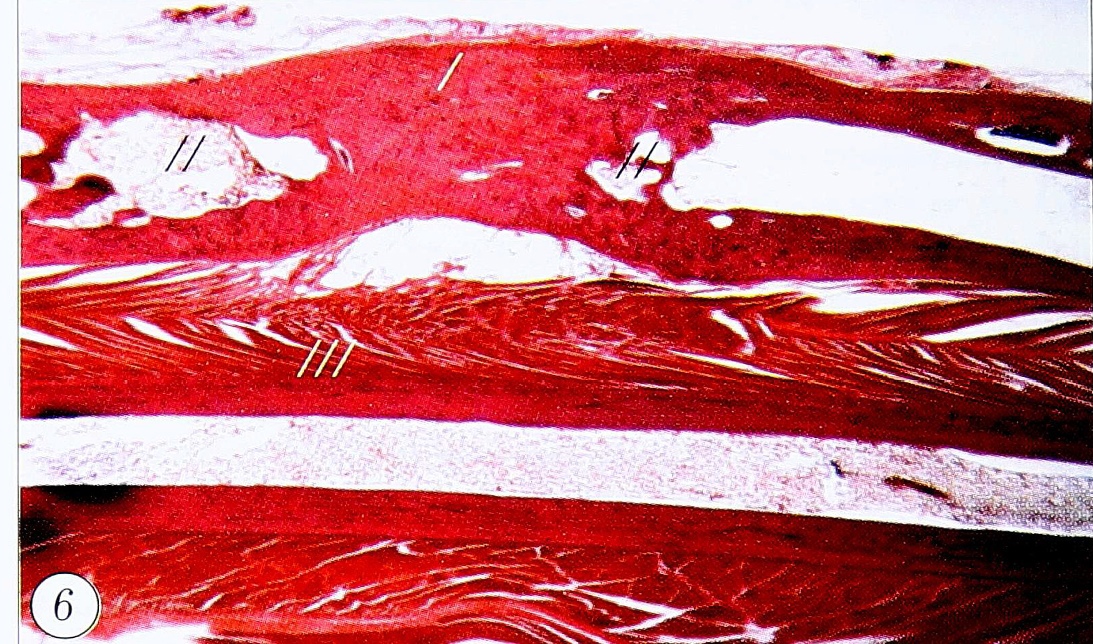

Рис. 6. Предплечье кролика, 16 нед после операции, 1-я опытная группа. Восстановленная лучевая кость. Участок новообразованной кости (/). Полости резорбции (//). Локтевая кость (///).

Через 16 нед после остеоэктомии рентгенологически тень регенерата заполняет весь дефект, имея более высокую плотность в его центральной части. При гистологическом исследовании обнаруживается, что центральная часть регенерата полностью состоит из компактной костной ткани, а его периферические части ремоделированы в трубчатую кость и консолидированы с проксимальным и дистальным костными отломками (рис. 6). Пространство между новообразованными кортикальными пластинками заполнено костным мозгом и является продолжением костномозгового канала костных отломков. Несмотря на отсутствие четкой границы, новообразованную кость можно определить по неупорядоченной ориентации сосудов, центральных каналов и остеонов. В центральной части регенерата встречаются зоны резорбции. Со стороны костномозгового канала проксимального и дистального костных отломков наблюдается «встречная» резорбция регенерата, т.е. происходит формирование в нем нового костномозгового канала. В локтевой кости какие-либо изменения в кортикальных пластинках и костном мозге отсутствуют, т.е. к 16-й неделе после операции наступает полное восстановление структуры кости в очагах резорбции.